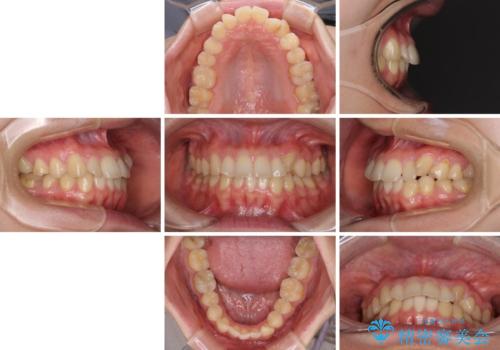

- 八重歯を気にして来院された患者様です。

診査を行ったところ、下顎前歯が1本欠損しており、下顎歯列が上顎よりも小さくなっていることで、上顎にデコボコが生じていました。

口元を見ると抜歯をして突出感を改善するような状態ではなかったため、上顎歯列のデコボコを整えて、歯列全体を後方に移動させることでバランスを取ることとしました。

マウスピース矯正は自己管理が煩わしいとのことで、ワイヤー装置にて矯正治療を行うこととしました。

思っていた以上に上顎歯列を後方に移動させることができ、すっきりとした口元に仕上げることができました。